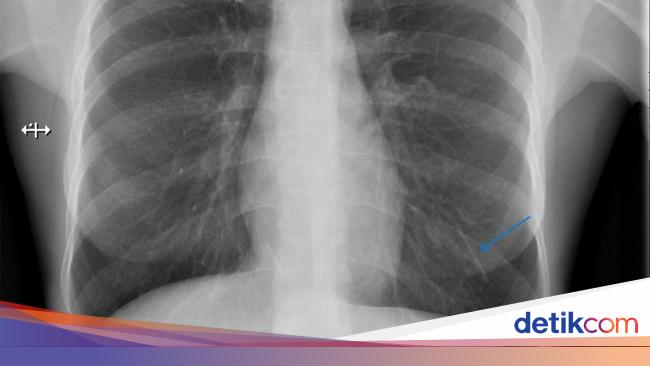

Alat KB implan wanita di Inggris bermigrasi dari lengan atas ke paru-paru kirinya. Diduga terlepas sekitar seminggu setelah ia menjalani prosedur tersebut.